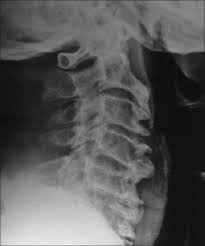

These are the kinds of x-rays we as chiropractors see every day. Pretty scary, huh? If you show these x-rays to a person in the medical field, they will say, "Oh, this person has osteoarthritis". Breaking down that label - osteo = bone, arth = joint, & itis = inflammation - your bone-joint is inflamed. But as chiropractors, we always ask, "Why?" Why did THAT joint degenerate but the one nearby - just as old as the other one - not have bone spurs?

Bone spurs or osteophytes, are bony projections that form off of the

bones of the spine, (vertebra) and joints of the extremities, (shoulders,

elbow, wrists, hip, knee, ankle and foot). They are the body's attempt to "shore up" an area of increased biomechanical stress by laying down more calcium.